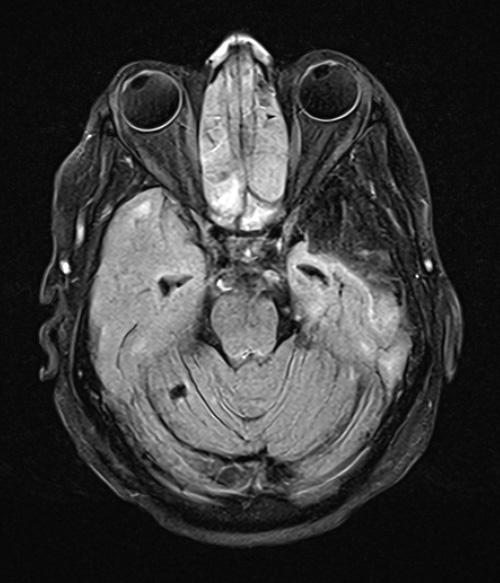

Notice the loss of the left basis pontis in these FLAIR scans.